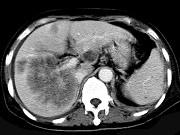

问题 男,42岁,中上腹痛,轻度黄疸,结合CT图像,提出最可能的诊断()

选项 A.肝脓肿 B.肝多发性囊肿 C.肝癌肝内转移伴门脉癌栓形成 D.胆管细胞癌 E.肝血管瘤

答案 C